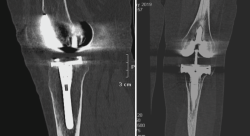

4. Prótesis (Figura 27)

Figura 27. Corte de reconstrucción sagital y coronal de tomografía axial computarizada de rodilla: se valoran los componentes femoral y tibial de la prótesis total.